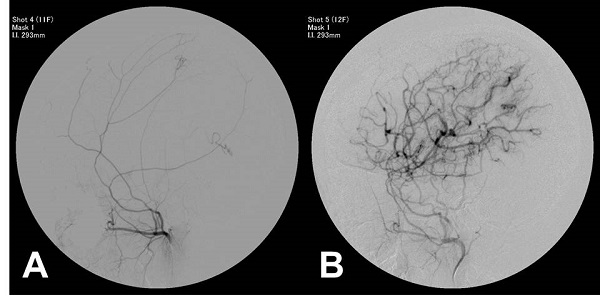

이번에 수술한 1000번째 환자는 12세 여아로 지난해 간헐적 위약과 경련으로 입원해 지난달 좌측 반구와 후두엽에 혈관간접문합 수술을 받았다. 건강한 모습으로 퇴원한 환자는 다음달 우측 반구 수술이 예정돼 있다.

모야모야병은 특별한 원인 없이 뇌에 피를 공급하는 혈관이 서서히 좁아져 막히는 병이다. 어린이들은 주로 일시적 마비 증상으로 병원을 찾게 되며, 두통, 경련이 나타나는 경우도 있다. 심한 경우 뇌경색과 뇌출혈도 동반된다. 수술후 80% 이상의 환자는 증상이 없이 정상적인 생활이 가능하다. 수술후의 통합적 관리가 요구된다.